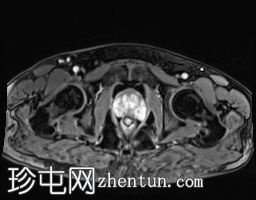

轴位

DWI

5.jpg

ADC

DWI/ADC:高b值DWI呈弥漫性高信号,ADC呈相应低信号(扩散受限)。评分5/5。

DCE:早期强化阳性。

PI-RADS:5 - 极高风险(极有可能存在临床意义的癌症),考虑炎症性病变。

肉芽肿性前列腺炎是多参数磁共振成像 (mpMRI) 中一种重要的、与临床意义显著的前列腺癌相似的疾病,因为它可以产生明显的周围带异常,伴有扩散受限和早期强化,通常导致较高的 PI-RADS 分级。

在本病例中,mpMRI 显示双侧周围带弥漫性 T2 低信号,高 b 值 DWI/ADC 图像上呈扩散受限,早期强化阳性,并伴有包膜轮廓隆起。这种影像学表现可能类似于浸润性或广泛性周围带癌,尤其是在 PSA 升高和直肠指检异常的情况下。然而,炎症性疾病,特别是肉芽肿性前列腺炎,可能出现类似的影像学表现。经直肠前列腺活检的组织病理学检查显示,患者患有严重的慢性非干酪性肉芽肿性前列腺炎,未见肿瘤证据。